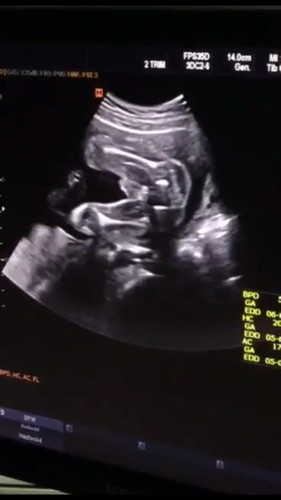

แบบนี้คือเพศชายชัวร์ๆเลยใช่ไหมคะ

แบบนี้คือผู้ชายชัวร์ๆเลยใช่ไหมคะแม่ๆ แอบลุ้นให้เป็นหญิงค้า ?

น่าจะเป็นจุ๊ดจู๋น้อยนะคะนั่น ชัดค่า มีลูกชายดีออกค่ะ คลอดออกมาแล้วเราจะตกหลุมรักเค้ายิ่งกว่าคนพ่ออีก

ชายชัวร์ จร้า จู๋โด้ แม่บ้านนี้ก็ อยากได้หญิง ซาวแย้วโชว์ไข่ โชว์จู๋ น้อยๆ เลยจร้า 555555 🤭😅🥰

คงไม่ต้องลุ้นเลย ผช.ชัดเจนมากแม่

ชายจ้าแม่ จู๋โผล่ชัดเจนเลย

ชัดมากค่ะแม่ ผู้ชายนะ

ชายค่ะจู๋ชัดมากค่ะ